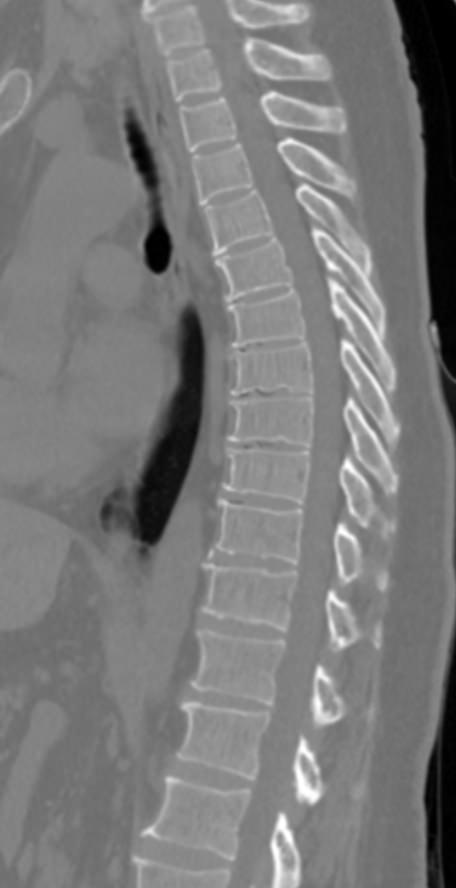

Мультиспиральная компьютерная томография является одним из наиболее информативных методов диагностики дегенеративно-дистрофических заболеваний, травматических, воспалительных изменений, а также опухолевых процессов позвоночника. Методика предусматривает использование рентгеновского излучения для получения детализированных снимков костных структур позвоночника, межпозвонковых суставов и межпозвоночных дисков.

При подозрении на распространенный процесс с поражением различных уровней позвоночного столба показано проведение мультиспиральной КТ трех отделов позвоночника.

В клинике «Доступная медицина» установлены современные мультиспиральные компьютерные томографы экспертного класса TOSHIBA AQUILION в различных модификациях (64-срезовый и 128-срезовый), на которых выполняются комплексные обследования позвоночника, включая одномоментное исследование несколько отделов. Аппараты производят сканирование с помощью рентгеновских лучей, делая тончайшие срезы с шагом от 0,5 мм, затем с помощью компьютерных программ полученные данные преобразуются в изображения трехмерного формата, что обеспечивает точность и достоверность диагностики.

С помощью мультиспиральной КТ можно диагностировать:

- дегенеративно-дистрофические заболевания позвоночника (остеоартроз, спондилез, деформирующий спондилоартроз);

- травматические повреждения позвоночника (компрессионные и оскольчатые переломы);

- стеноз (сужение) позвоночного канала;

- грыжи межпозвонковых дисков (протрузии, экструзии и грыжи Шморля);

- спондилиты, гнойные артриты, сакроилеит, абсцессы околопозвоночных тканей и другие воспалительные заболевания, туберкулез;

- хронические системные заболевания позвоночника (болезнь Бехтерева);

- опухоли позвоночника и окружающих тканей;

- патологические изгибы позвоночника, сколиоз, усиленный или выпрямленный лордоз как нарушение статической функции позвоночника;

- аномалии строения позвоночника.